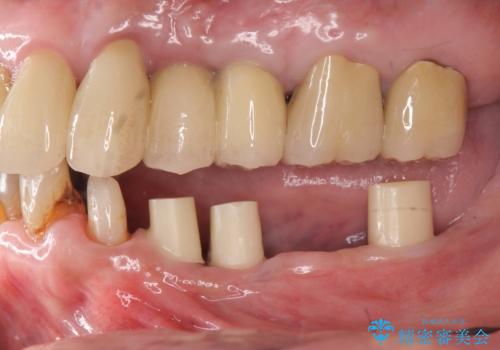

虫歯による歯の喪失 インプラントによる咬合機能回復

虫歯の徹底的な除去、安定した噛み合わせを達成するインプラント治療、深い虫歯、根管治療といった複数の治療項目を一つづつ積み重ね、長期的な予後を目指します。

複雑な問題点に対する明確な治療目標を立てることで、最終的に長い予後を期待できる治療を達成することができます。